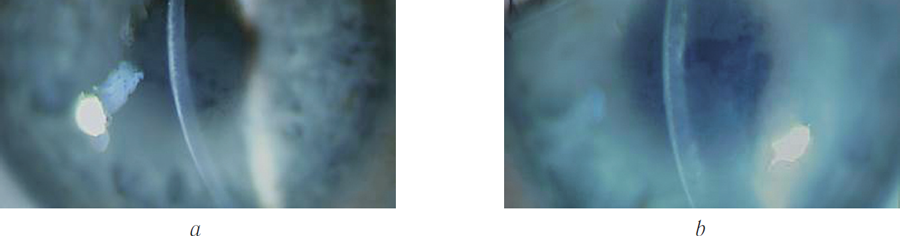

Group 1 included patients with primary Fuchs ECD (clinical examples showing the cornea are shown in Figures 1 and 2), whereas group 2 comprised patients with secondary ECD (clinical examples are shown in Figures 3 and 4).

Fig. 3. Patient D., 64 years, with the secondary ED before treatment

Fig. 4. Patient K., 68 years, with the secondary ED before treatment

All patients in group 2 (six eyes) had no positive dynamics 8 months postoperatively, although the initial condition of their cornea was the same as in group 1 patients (Figures 9 and 10). These patients underwent penetrating keratoplasty.

Fig. 9. Patient S., 77 years, with the secondary ED 8 months after the isolated DR and ACXL with negative dynamics

Fig. 10. Patient R., 68 years, with the secondary ED 8 months after the isolated DR and ACXL with negative dynamics